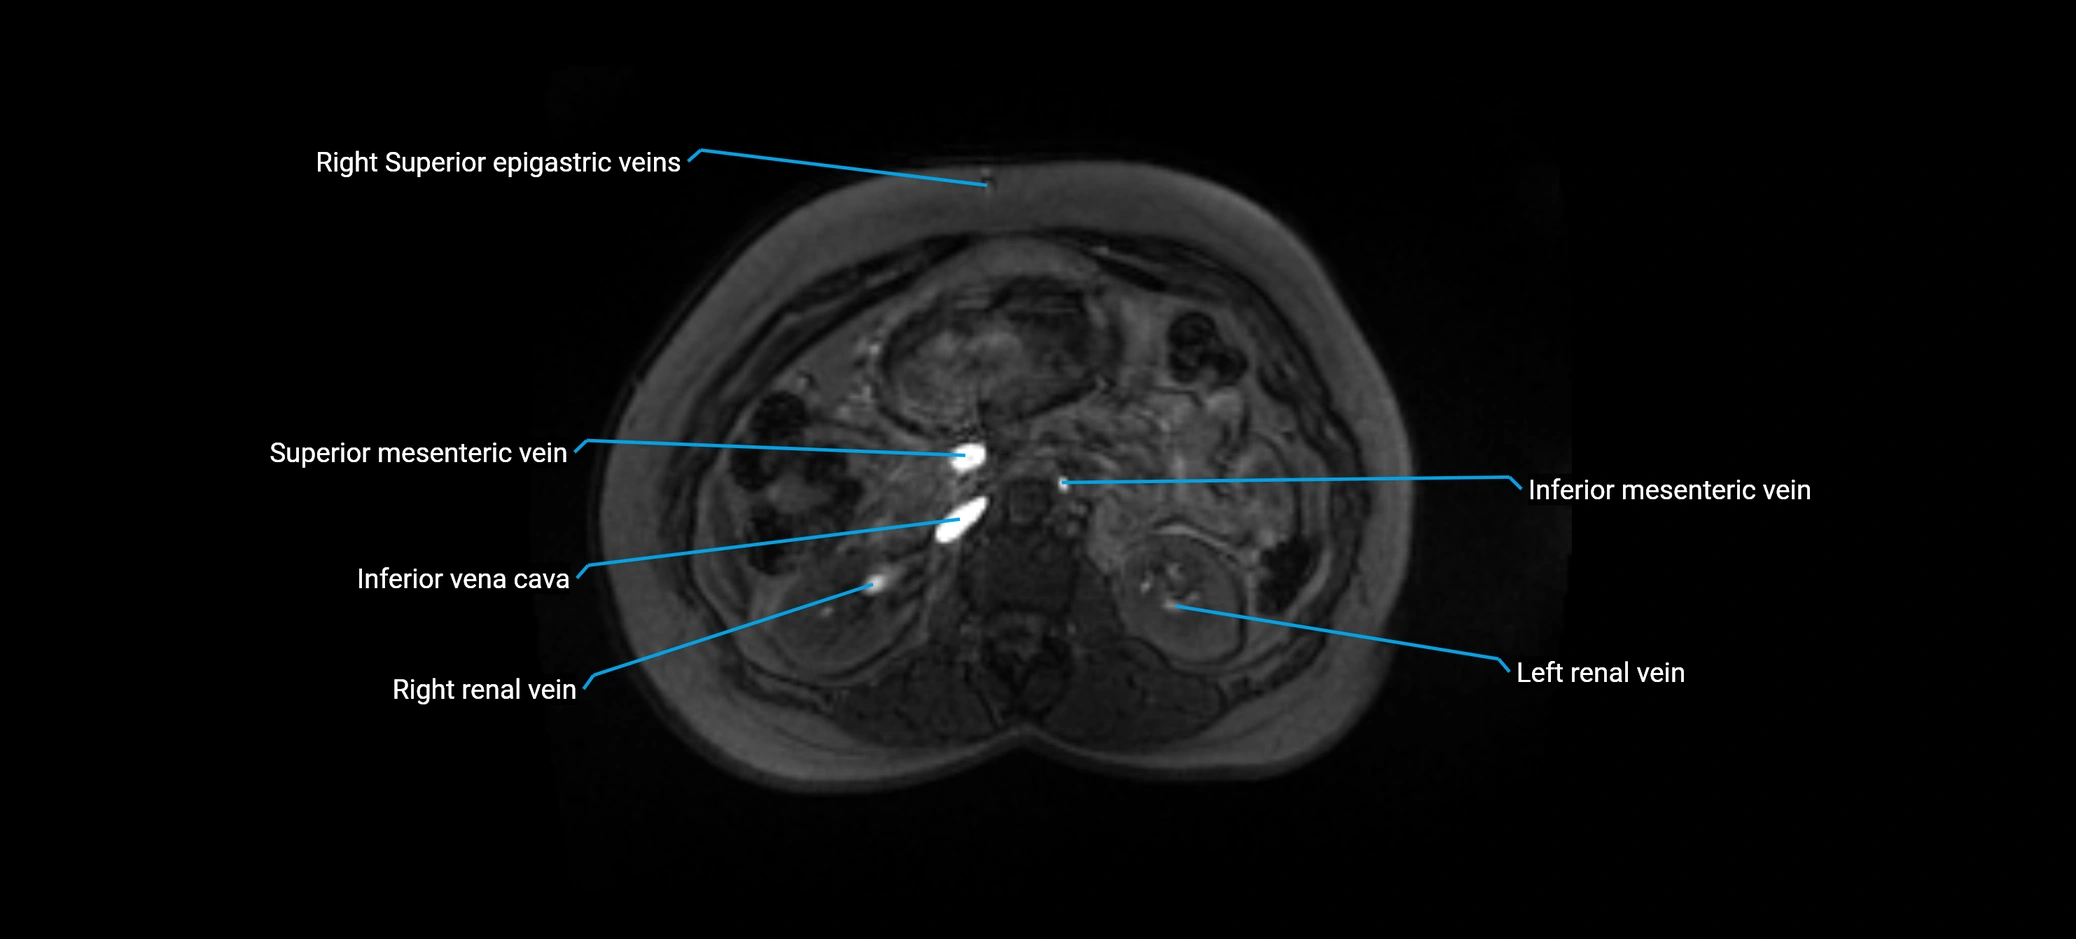

MRI image

image